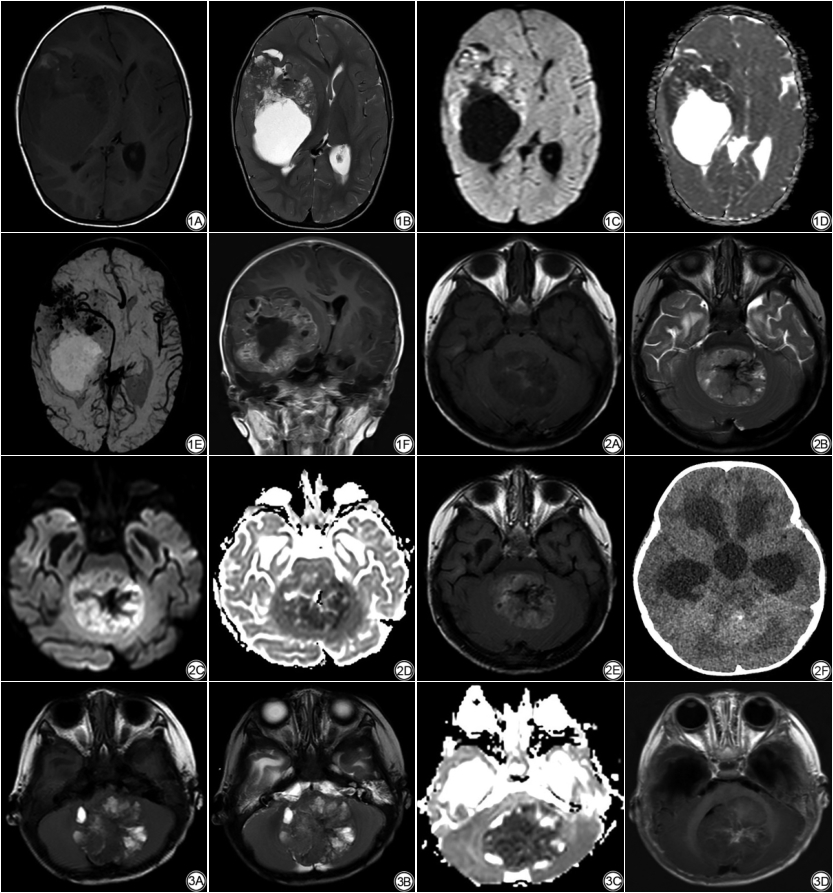

患儿中位年龄19个月,年龄范围5个月~39个月,原发灶位于幕下5例,幕上1例,幕上、幕下同时受累3例。瘤体最大径49.9±18.3 mm,伴有偏心囊变7例,瘤体出血6例,脑转移3例,脑、脊髓同时转移1例;瘤体实性成分在CT上以等或高密度为主,MRI T2WI信号混杂,DWI上瘤体实性成分呈高信号,ADC图为低信号,瘤体强化模式多样。

5例幕下肿瘤位于左桥臂1例,小脑蚓4例,其中1例小脑蚓肿瘤伴有右颞枕叶及脊髓转移;1例幕上肿瘤位于右额颞叶脑实质内;3例幕上幕下同时受累肿瘤:1例沿中脑导水管、第四脑室铸型生长并伴蛛网膜下腔、小脑半球多发转移结节,1例沿四叠体池和第三脑室生长同时伴有左侧脑室转移,1例位于第四脑室和第三脑室后部同时伴有左颞叶单发转移结节。9例肿瘤原发灶最大径30~90 (49.9±18.3) mm。

8例患儿头颅CT平扫示肿瘤实性成分呈等密度1例,高密度4例(图2F,4A),混杂密度3例,5 (5/8)例可见点状钙化(图2F);1例患儿初就诊时头颅CT平扫未见明确病灶,7个月后头颅MR平扫+增强发现右额颞叶巨大囊实性占位性病变(图1A~F)。

肿瘤实性为主7例、囊实性2例;8例有明确囊变,囊变分布于外周6例(图1B,2B,3B,4A)、分布于中央1例、弥漫分布小囊变1例;6例伴有瘤内出血(图1E,2B,3A),其中1例相应SWI幅值图表现为多发斑片状明显低信号(图1E);伴有脑转移3例,同时伴有脑、脊髓转移1例(图4C,4D);病变在T1WI上呈等信号3例,稍低信号1例(图2A),混杂信号5例(图1A,3A),T2WI上呈等信号3例,混杂信号6例(图1B,2B,3B);高b值DWI上,瘤体实性成分呈中等高信号2例,明显高信号7例(图1C,2C),9例ADC图均表现为明显低信号(图1D,2D,3C),对应平均ADC值(ADCmean)范围为(0.42~0.60)×10-3 mm2/s;伴有明显瘤周水肿1例(幕上脑实质病变),伴轻中度瘤周水肿5例,无明确瘤周水肿3例;伴有幕上脑室扩张6例,其中5例同时伴有不同程度室旁水肿;增强扫描肿瘤实性成分不均匀强化,其中轻中度强化4例(强化区域分布:沿实性区域弥漫分布2例,条片状分布1例,环形曲带样分布1例),明显强化5例[中央放射状分布1例(图3D),多结节堆积状分布2例,环形曲带样分布2例(图1F,2E)]。

既往通常认为AT/RT缺乏特异性影像学表现,随着对其认识不断加深,AT/RT具有一些相对特异性的影像表现,可能有助于提高其诊断率。AT/RT发病部位无特异性,可以发生在中枢神经系统的任何位置,多呈局灶性发病,表现为幕上或幕下肿块,也可以同时累及幕上、幕下,与本组部分病例肿瘤跨越幕上、幕下生长相似[7]。AT/RT肿瘤体积通常较大,本组病例瘤体最大径约30.0 mm~90.0 mm,首次就诊时瘤体最大径均在30 mm以上。有学者认为偏心分布囊变是AT/RT较为特征性的影像表现[16,17],亦有学者通过比较分析AT/RT和髓母细胞瘤中囊变的分布特点,证实前者囊变偏心分布更常见[18],本组有明确囊变病例中,偏心分布7例(7/8),与文献报道AT/RT易发生偏心囊变相符。本组病例伴有出血6例(6/9),与文献报道AT/RT容易发生出血坏死,约45%~63%患儿可见瘤体出血相符[7,16]。值得一提的是本组一名17个月龄男患儿初次就医时(主诉:颅缝狭窄)头颅CT未见明确占位性病变,7月后再次就诊(嗜睡、左侧肢体无力)行头颅MR平扫+增强发现右额颞叶巨大囊实性占位性病变,短短半年时间肿瘤迅速生长最大径达9.0 cm,说明该肿瘤细胞增殖活跃,与此类肿瘤Ki-67较高相符。AT/RT肿瘤细胞密集、核质比高,高b值DWI上肿瘤内水分子扩散受限明显加重呈高信号,对应ADC呈明显低信号。多项研究显示中枢神经系统AT/RT的ADC图表现为明显低信号,其ADC值范围约(0.45~0.85)×10-3 mm2/s,本组9例患儿范围(0.42~0.60)×10-3 mm2/s [ADCmean为(0.51±0.06)×10-3 mm2/s],与文献报道一致性较高[7,19,20]。文献报道曲带样环形强化在AT/RT中具有特异性,亦有学者称之为“盘山公路征”[16],我们的病例中有2例(2/8)表现为曲带样强化,与文献报道类似。此外,我们的病例中还可见其他多种强化方式,相似表现为肿瘤整体不均匀轻中度或明显强化,但强化模式多样,如中央放射状强化、多结节堆积样强化、局部条片样强化等。AT/RT易随脑脊液循环播散转移至脑内其他部位或脊髓,部分患儿初就诊时常伴有脑脊液播散灶[21],本组病例首次就诊时1例同时伴有脑组织、脊髓转移,3例伴有脑转移(脑实质转移1例,脑室转移1例,脑实质和蛛网膜转移1例)。Nowak等通过对43名已知分子亚型AT/RT进行影像学对比分析发现:ATRT-MYC亚型较其他两种亚型有更显著的瘤周水肿,而ATRT-SHH和ATRT-TYR亚型偏心囊变更见,ATRT-TYR和ATRT-MYC亚型有明显强化趋势而约三分之一ATRT-SHH亚型增强后无确切强化[22]。本组回顾性病例患儿未作相应基因型检测,无法与该文研究结果进行对比,以后的工作中对ATRT基因分型的应用有助于我们更深层次地认识AT/RT。